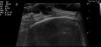

Una mujer de 61 años de edad intervenida de un fibroadenoma de mama, sin otros antecedentes médicos de interés, consultó por una lesión discretamente dolorosa, de rápido crecimiento en la región frontoparietal derecha pegada a la línea de implantación capilar. La lesión tenía un mes de evolución y había aparecido pocos días después de un traumatismo sobre la zona. En la exploración física presentaba una lesión exofítica de 15mm de diámetro, bien delimitada, de tonalidad roja y violácea, con parches blanco-amarillentos y blanda al tacto (fig. 1). La imagen dermatoscópica mostraba una lesión con áreas rojizas homogéneas, estructuras blanco amarillentas irregulares, zonas de velo azul blanquecino, vasos lineales irregulares y algunas crisálidas (fig. 2). En la ecografía cutánea se observó una lesión hipoecoica lobulada localizada en la dermis superficial, con discreto refuerzo posterior y aumento de la vascularización perilesional (fig. 3). Se realizó extirpación completa de la lesión bajo anestesia local para análisis histopatológico, que confirmó el diagnóstico de sospecha de pilomatrixoma anetodérmico (fig. 4).

La imagen ecográfica clásica del pilomatrixoma convencional es una lesión con halo hipoecoico y una zona central hiperecoica (correspondiente a calcificación) que genera sombra posterior5. Hughes et al. publican en 1999 un trabajo retrospectivo sobre ecografía preoperatoria de 28 lesiones sospechosas de pilomatrixomas convencionales6. En 20 de ellas la ecografía apoyaba el diagnóstico clínico de sospecha y en 16 de esas 20 lesiones se pudo realizar estudio histológico que confirmó el diagnóstico de pilomatrixoma. En la literatura revisada no se ha encontrado una descripción de la ecografía cutánea del pilomatrixoma anetodérmico.

En cuanto al diagnóstico diferencial, se puede plantear con el carcinoma basocelular (CBC) o el melanoma4, y en ambos casos los estudios dermatoscópico y ecográfico pueden ayudar en el diagnóstico preoperatorio. Desde el punto de vista ecográfico el CBC y el melanoma se describen también como lesiones hipoecoicas. Las características que pueden ayudar a diferenciarlas, son la presencia de unos pequeños nódulos hiperecoicos en el interior de la lesión característicos del CBC y un borde irregular con abundante vascularización en el interior del tumor en el melanoma7,8.